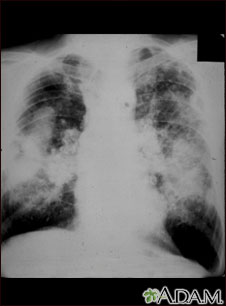

This picture shows complicated coal workers pneumoconiosis. There are diffuse, massive light areas that run together in the upper and middle parts of both lungs. These are superimposed on a background of small and poorly distinguishable light areas that are diffuse and located in both lungs. Diseases which may explain these x-ray findings include, but are not limited to: complicated coal workers pneumoconiosis (CWP), silico-tuberculosis, and metastatic lung cancer.